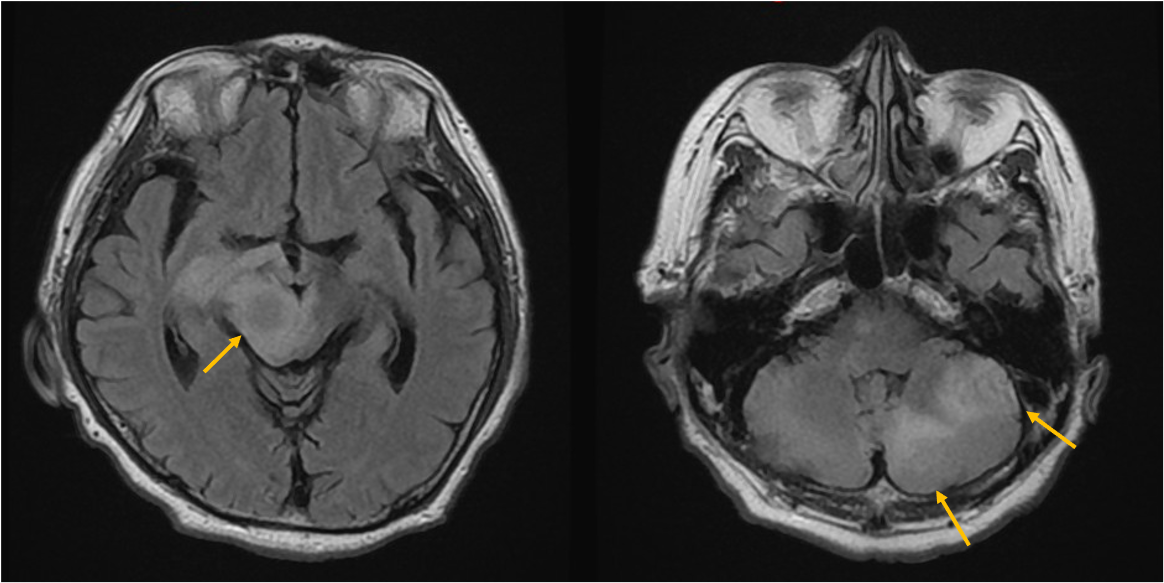

症例は70歳代男性。物が二重に見える、ふらつくとの訴えで来院。非造影MRIにて脳幹部や小脳に4個の多発脳腫瘍が認められ、症状と合致した。全身精査にて進行胃癌が発見され、その脳転移と診断された。放射線治療の適応判定のため造影MRIを施行し、新たに大脳に3個の微小転移が同定された。病変のサイズ・分布から微小転移を含む7個の腫瘍に対して定位放射線治療が可能と判断され、速やかに治療導入に至った。

本症例では先行する非造影MRIにて右中脳や左小脳の多発腫瘤が指摘され、周囲に浮腫を伴うことから転移が疑われていたが、病変数や大きさ・範囲ははっきりしなかった。造影MRIを実施することにより、右中脳に1個、左小脳に3個の2㎝大の輪郭の明瞭な腫瘍が確認されたほか、1㎝未満の3個の微小病変を新たに検出できた。非造影MRIを見直したところ7㎜の結節はFLAIRでも淡い高信号を示していたが質的診断は困難であった。3㎜の病変は非造影MRIでは存在診断不能であった。微小病変のうち2個は高位前頭葉の機能的に重要な部位に位置しており、治療適応と考えられた。造影MRIにより腫瘍の正確な個数とサイズ、分布の正確な情報を確認した後、定位放射線治療が可能と判断され、3D-FSPGR画像を治療計画に利用して迅速に治療が開始された。